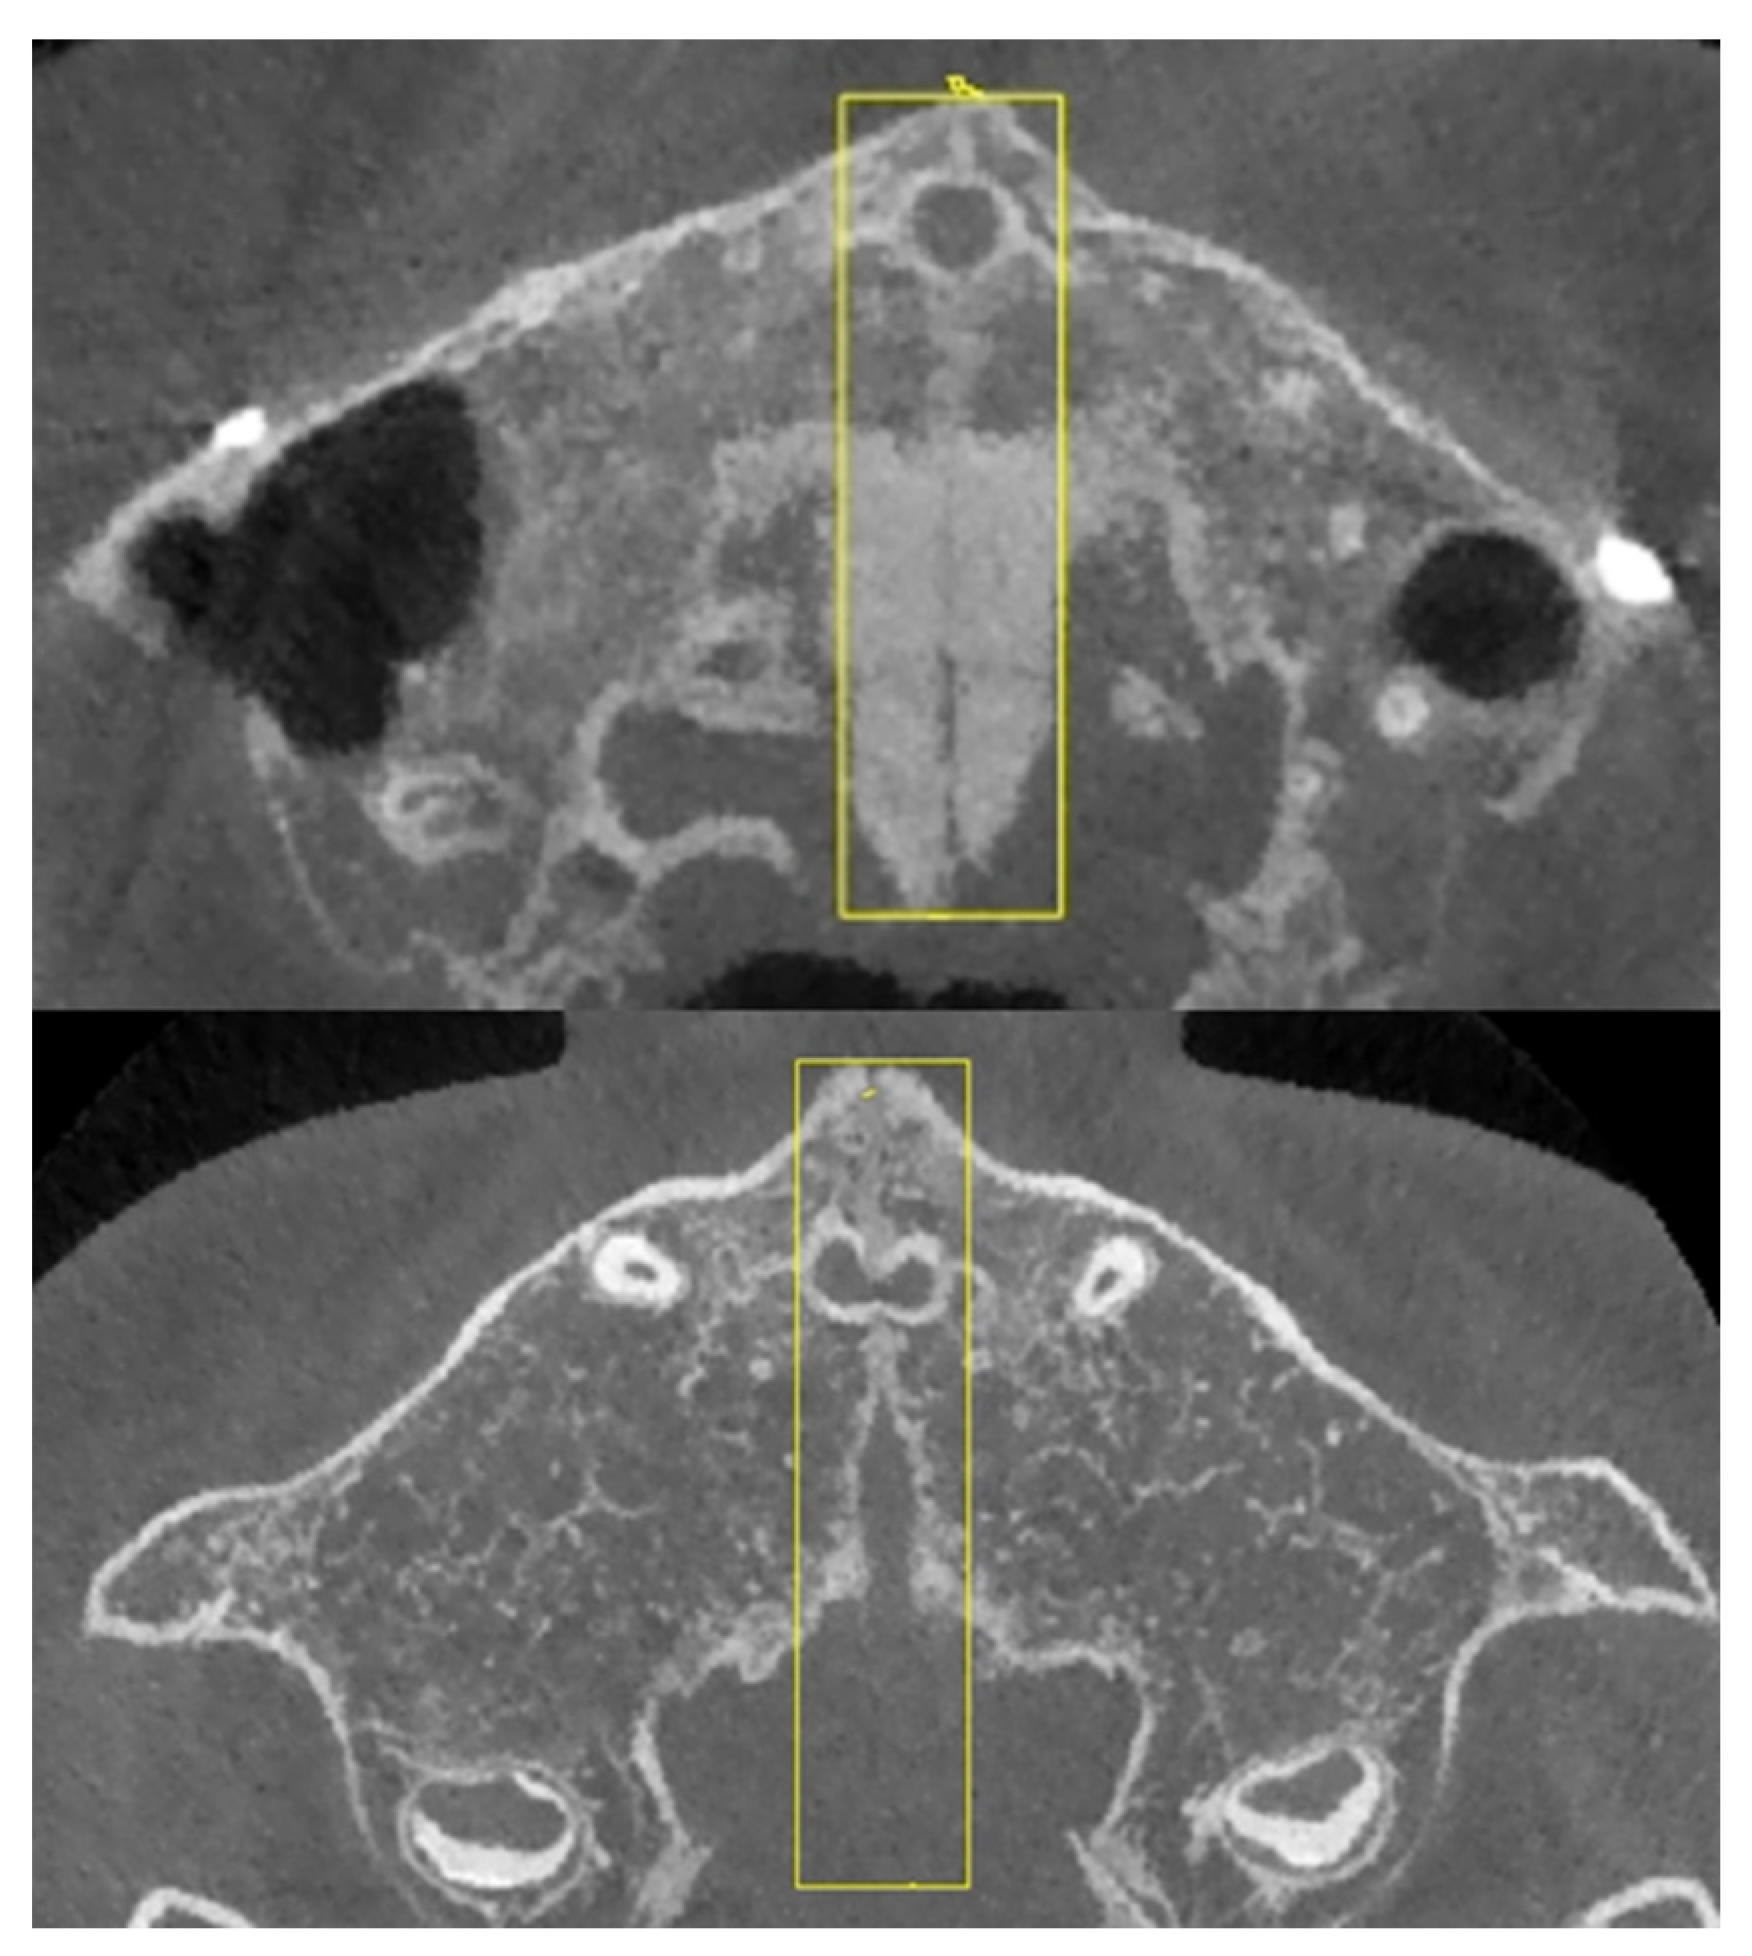

3.2. Midpalatal Suture ROI Extraction and Image Fusion Algorithm

4.1. Innovative Midpalatal Suture Image Fusion Algorithm

- We designed a midpalatal suture CBCT image fusion algorithm to utilize multi-slice valuable image information to improve the appraisal accuracy of midpalatal suture maturation and ossification status. This algorithm avoids the influence of CBCT examination orientation and the convex palatal vault, thus helping to show the overall perspective of midpalatal suture in one fused image.